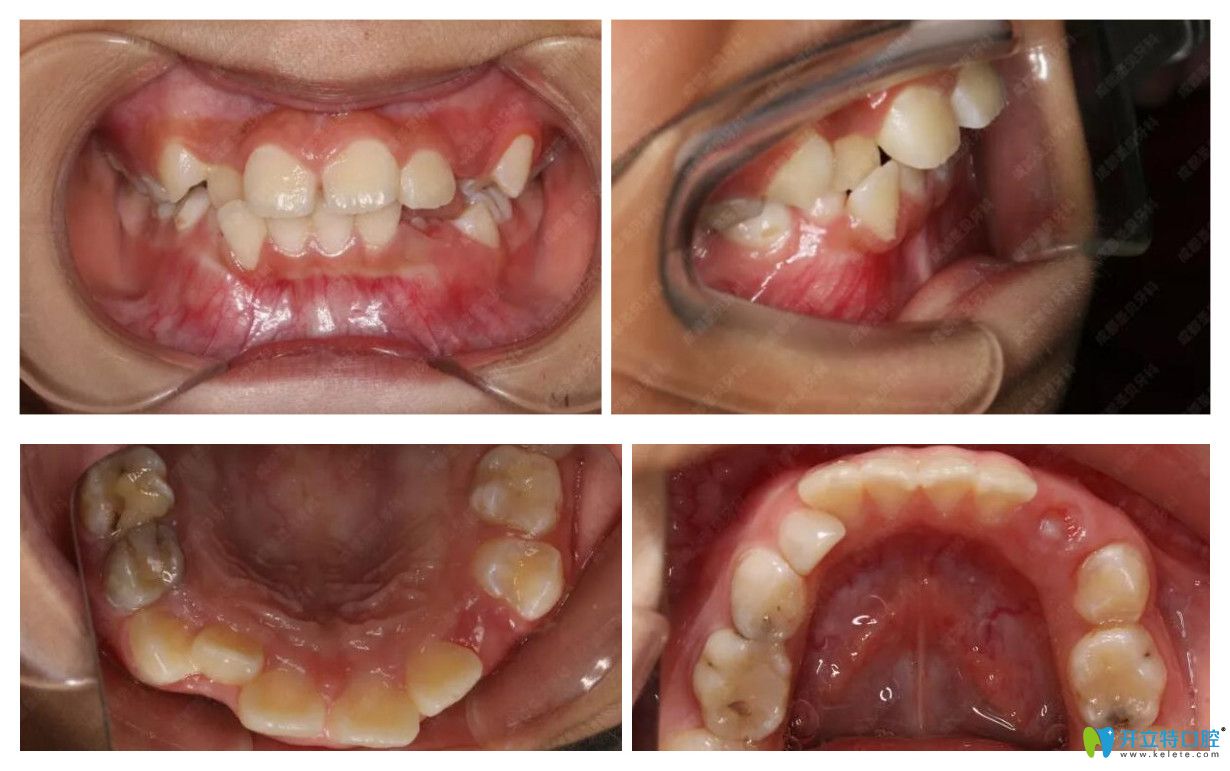

矯正前樣子:

正畸前口腔照片:

矯正前,不難看出孩子有輕微齙牙、門牙縫隙、牙列擁擠不齊、個(gè)別牙列反合。